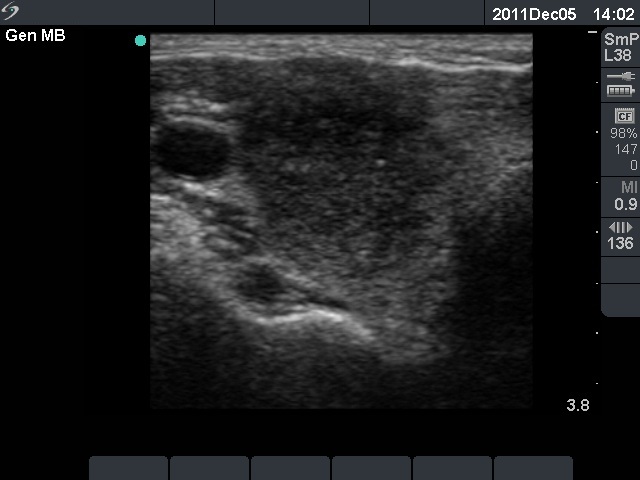

Initial examination (first row of images):

Clinical presentation: A 29-year-old woman requested a second opinion. She was in the 11th week of her pregnancy. She had mild neck discomfort for 2 months. A suspicious nodule was found in the left lobe on the evaluation. Aspiration cytology was repeatedly non-diagnostic. She was told that she had thyroid carcinoma with great probability. Her endocrinologist recommended to abort the child and then to undergo thyroidectomy.

Palpation: The left thyroid was hard on palpation, but not painful.

Ultrasonography: The right thyroid was echonormal and contained several small, insignificant lesions. There was a hypoechogenic lesion with blurred borders in the central and in the ventro-medial part of the left thyroid with increased intranodular blood flow.